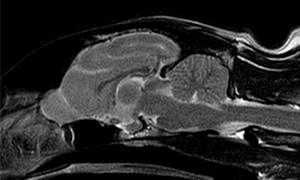

<MRIって?>

MRIは磁気共鳴画像診断とも呼び、強力な磁力と電波により臓器や血管などを画像化する検査。

MRI検査・脳脊髄検査を実施したが、脳に発作を起こすような異常は認められなかった。